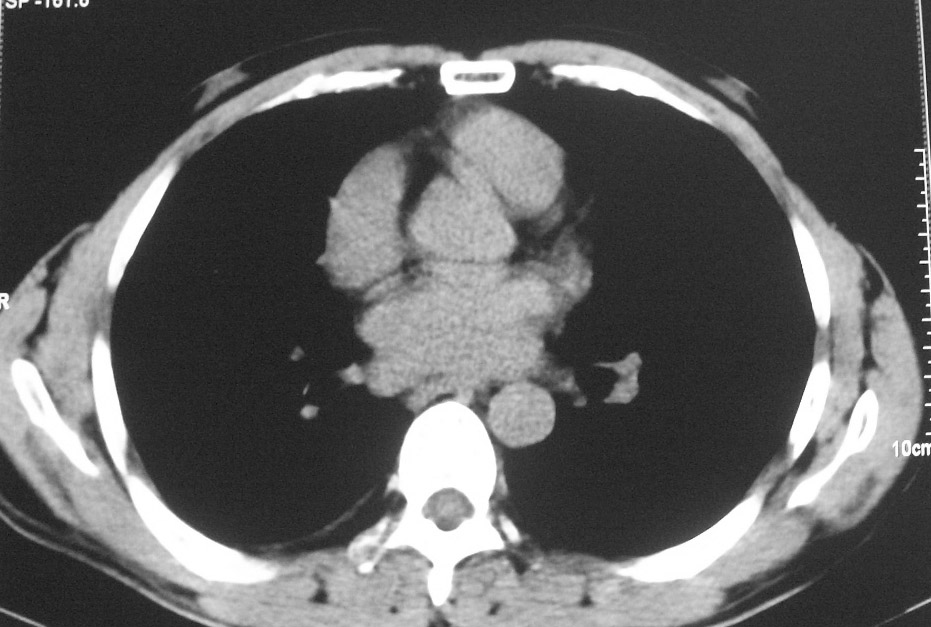

标题: CT5485:[原创]肺部占位请讨论

右肺上叶中央型肺癌并上叶肺不张、纵隔淋巴结肿大

右上叶支气管后壁明显增厚,支持右肺上叶中央型肺癌伴右上叶肺不张、纵隔淋巴结肿大。

右肺上叶中央型肺癌并上叶肺不张

右肺上叶中央型肺癌并上叶肺不张、纵隔淋巴结肿大.右侧少量胸腔积液。

右上肺中心型肺癌并肺不张,纵膈淋巴结肿大。右侧少量胸腔积液。

右肺上叶中央型肺癌并上叶肺不张。

中央型肺癌伴肺不张

右肺上叶中央型肺癌并阻塞性炎症、阻塞性肺不张……